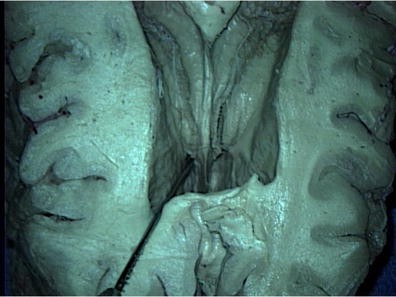

Superior view of an axial section through a cadaveric brain noting the right foramen of Monro (tip of needle)